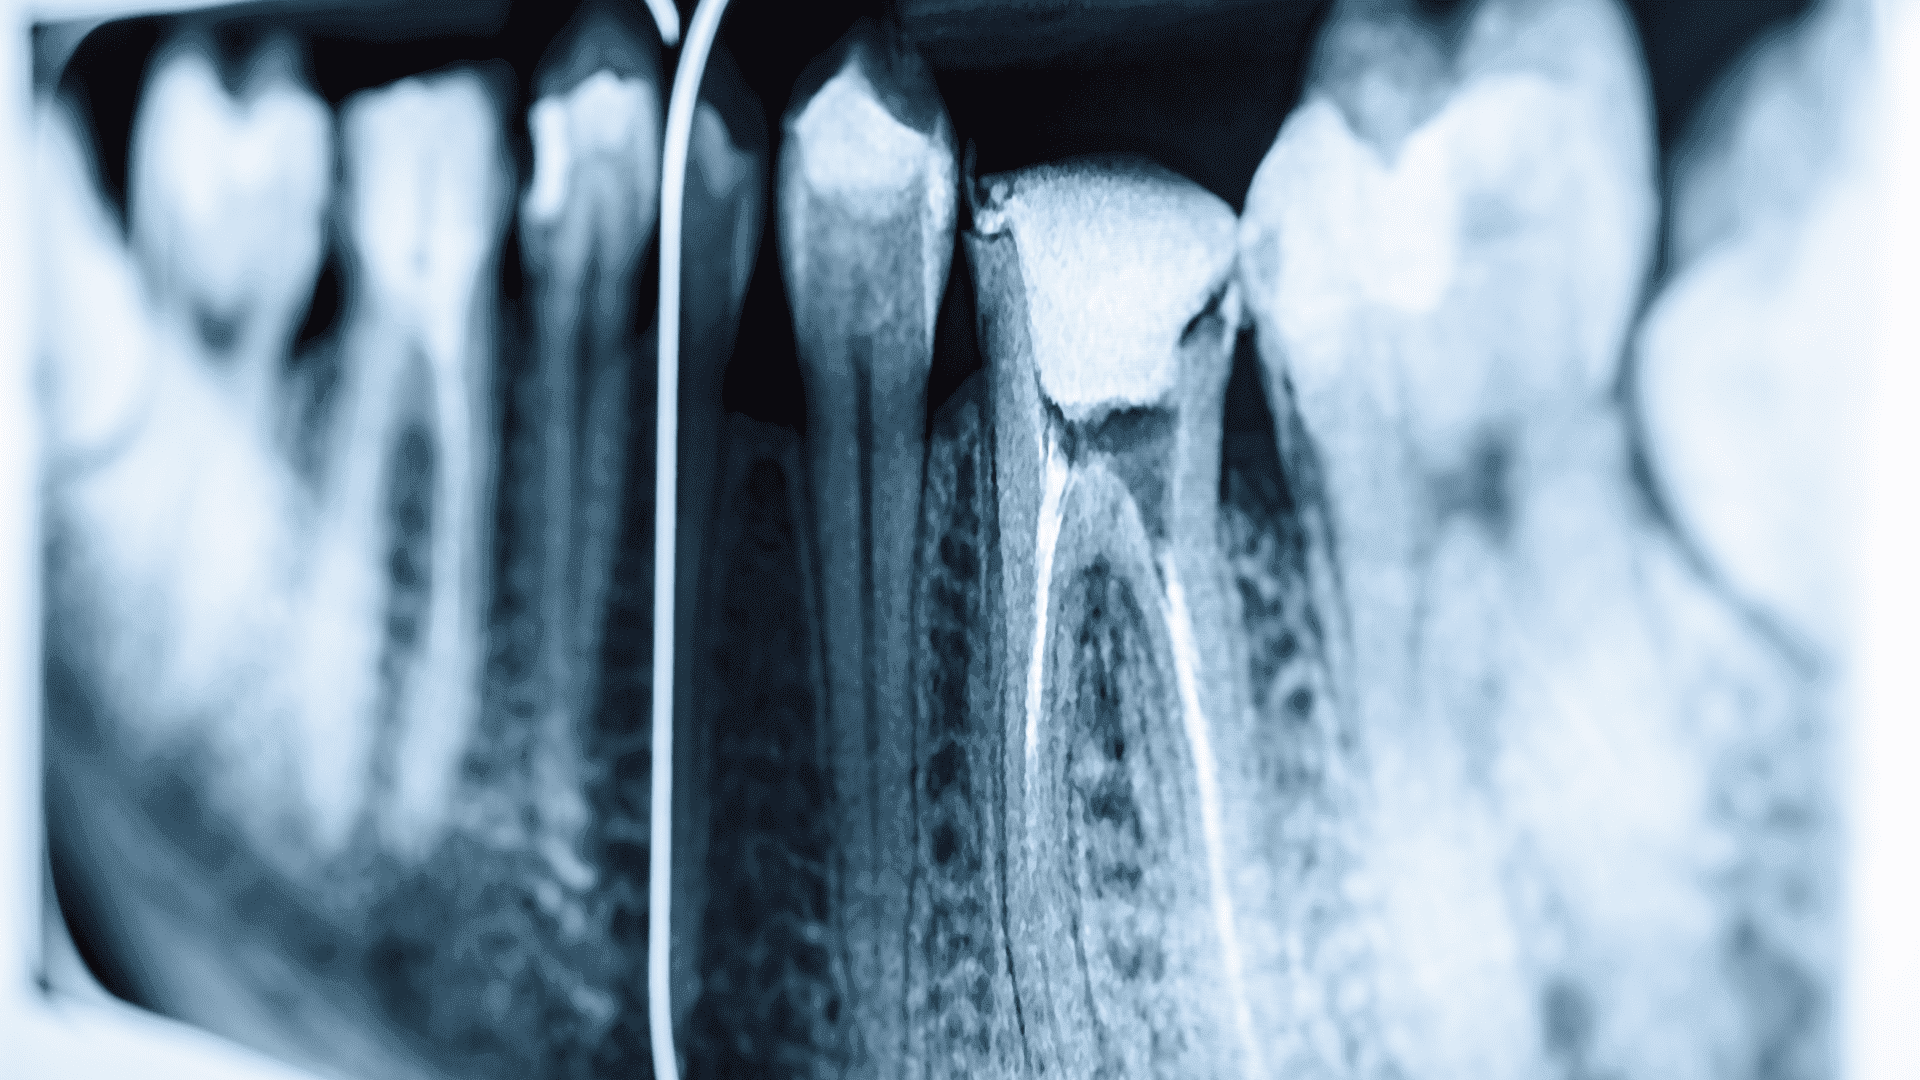

Zdjęcie punktowe RTG stanowi fundament nowoczesnej diagnostyki stomatologicznej, umożliwiając szczegółową ocenę stanu zdrowia zębów i tkanki kostnej szczęki oraz żuchwy. Ta technika radiologiczna skupia się na konkretnym obszarze zainteresowania, dostarczając obraz o wysokiej rozdzielczości, co jest nieocenione w precyzyjnym planowaniu leczenia. Od identyfikacji próchnicy po zaawansowane diagnozy chorób periodontologicznych i endodontycznych - zdjęcia punktowe RTG są niezbędnym narzędziem w rękach każdego dentysty. Ich niskie dawki promieniowania oraz szybkość wykonania sprawiają, że są one zarówno bezpieczne, jak i wygodne dla pacjentów.

Zdjęcia punktowe RTG wykorzystują zaawansowaną technologię radiologiczną do generowania szczegółowych obrazów pojedynczych zębów i ich bezpośredniego otoczenia. Dzięki zastosowaniu specjalistycznych aparatur RTG, które koncentrują wiązkę promieni na bardzo małym obszarze, możliwe jest uzyskanie wyraźnych i dokładnych obrazów, przy znacznie niższej dawce promieniowania w porównaniu do tradycyjnych metod radiologicznych. Nowoczesne urządzenia do RTG punktowego są również wyposażone w cyfrowe systemy przetwarzania obrazu, co pozwala na natychmiastowy podgląd wyników i ich łatwą archiwizację w cyfrowej dokumentacji pacjenta.